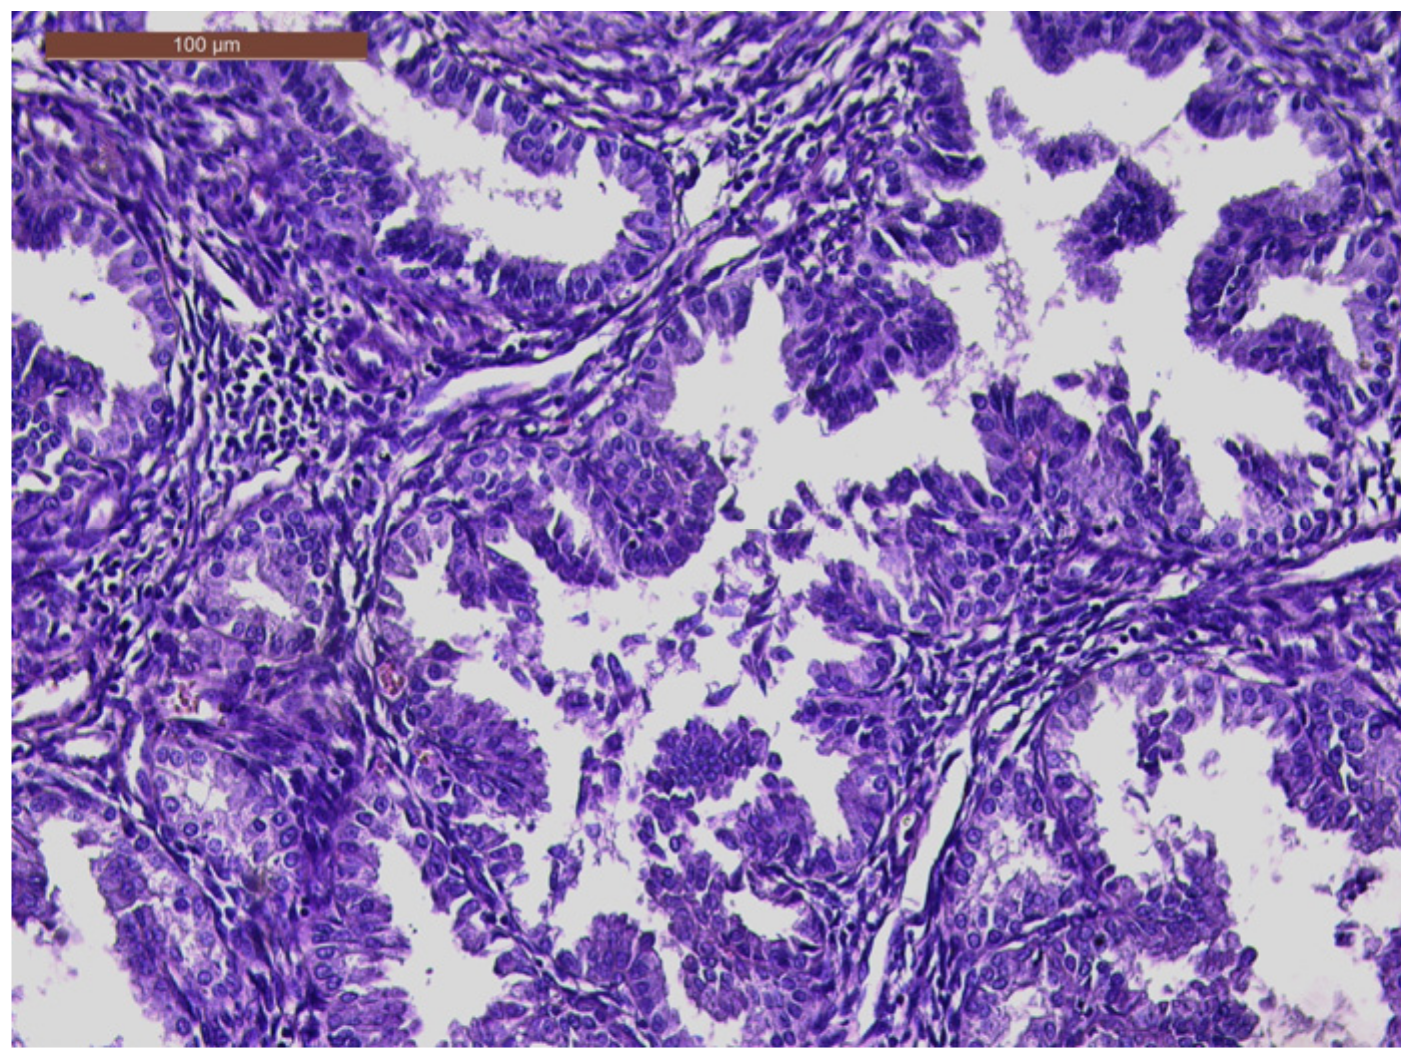

An MRI was performed that described a solid expansive formation, well delimited, with an inhomogeneous structure, with small cystic areas and an intense contrast socket. The mass was located in the vagina, apparently originating from the cervical level, with which it communicates over a distance of 4 mm, presenting the overall dimensions of 44/47/47 mm. The uterine body, the ovaries, and the pelvic organs were within normal limits. No images of pelvic adenopathies were revealed (Figure 2).

Figure 2. MRI examination (A); Sagittal section: the mass originating from the cervical level with small cystic areas (B); Coronal section: the vaginal mass with small cystic areas (C).